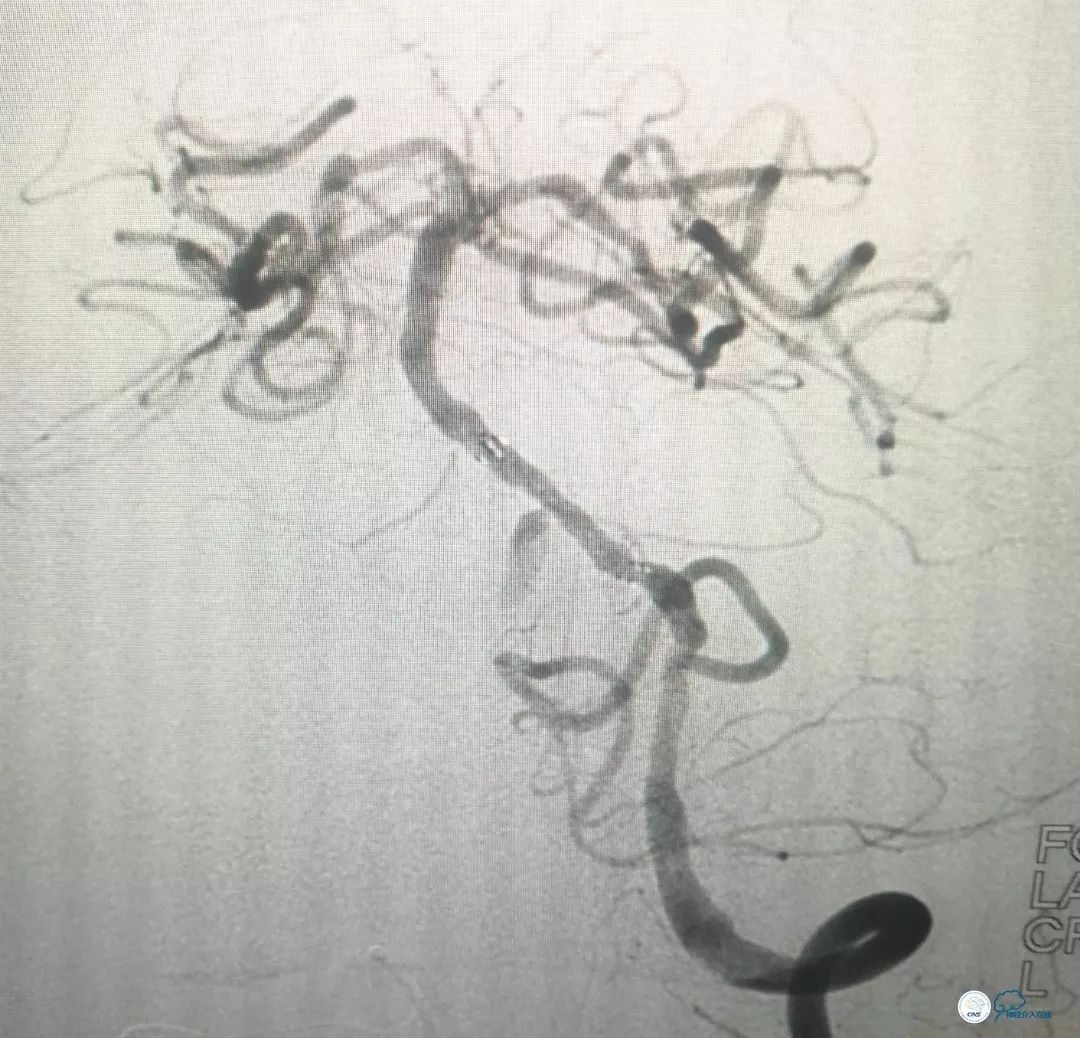

撤出球囊导管,送入wingspan (2.5mm x 15mm )自膨式支架,造影提示支架释放后支架贴壁良好,前向血流TICI 3级。右椎动脉V4段经返流显影,但病变受支架影响显示狭窄程度加重(图10)。

图10